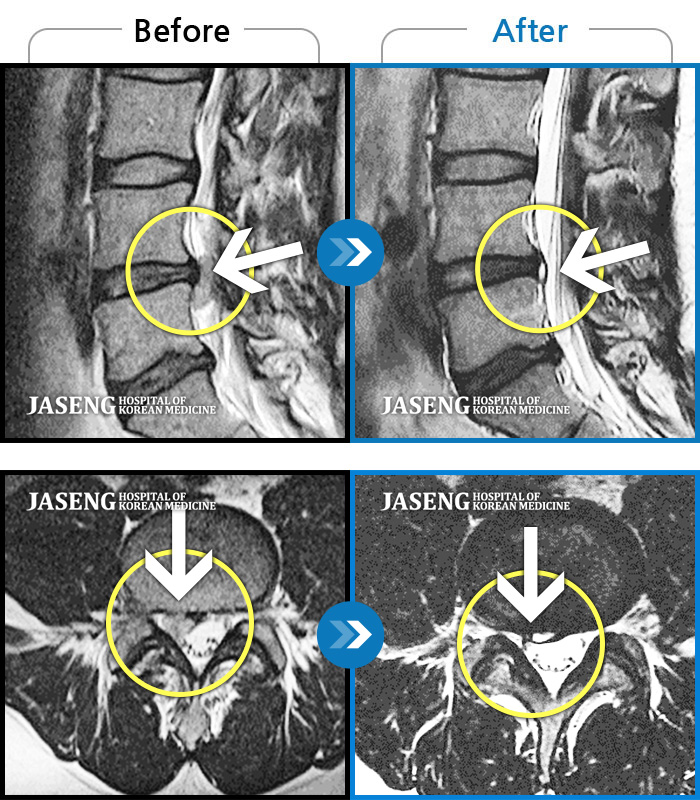

[뱸] 19.11.28~25.05.06

ȯںп Ǹ ǿ ԿǾ, ο ġ ۿ Ƿ ġḦ Ͻñ ٶϴ.